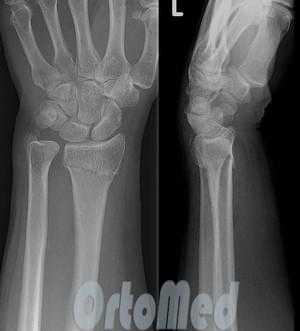

У 3 пациентов перелом головки лучевой кости сопровождался сопутствующим повреждением связочного аппарата локтевого сустава с вывихом предплечья. Вправление вывиха предплечья проводили сразу после поступления больного в стационар. Оперативное лечение выполнялось на 3-5 сутки (рис. 2).